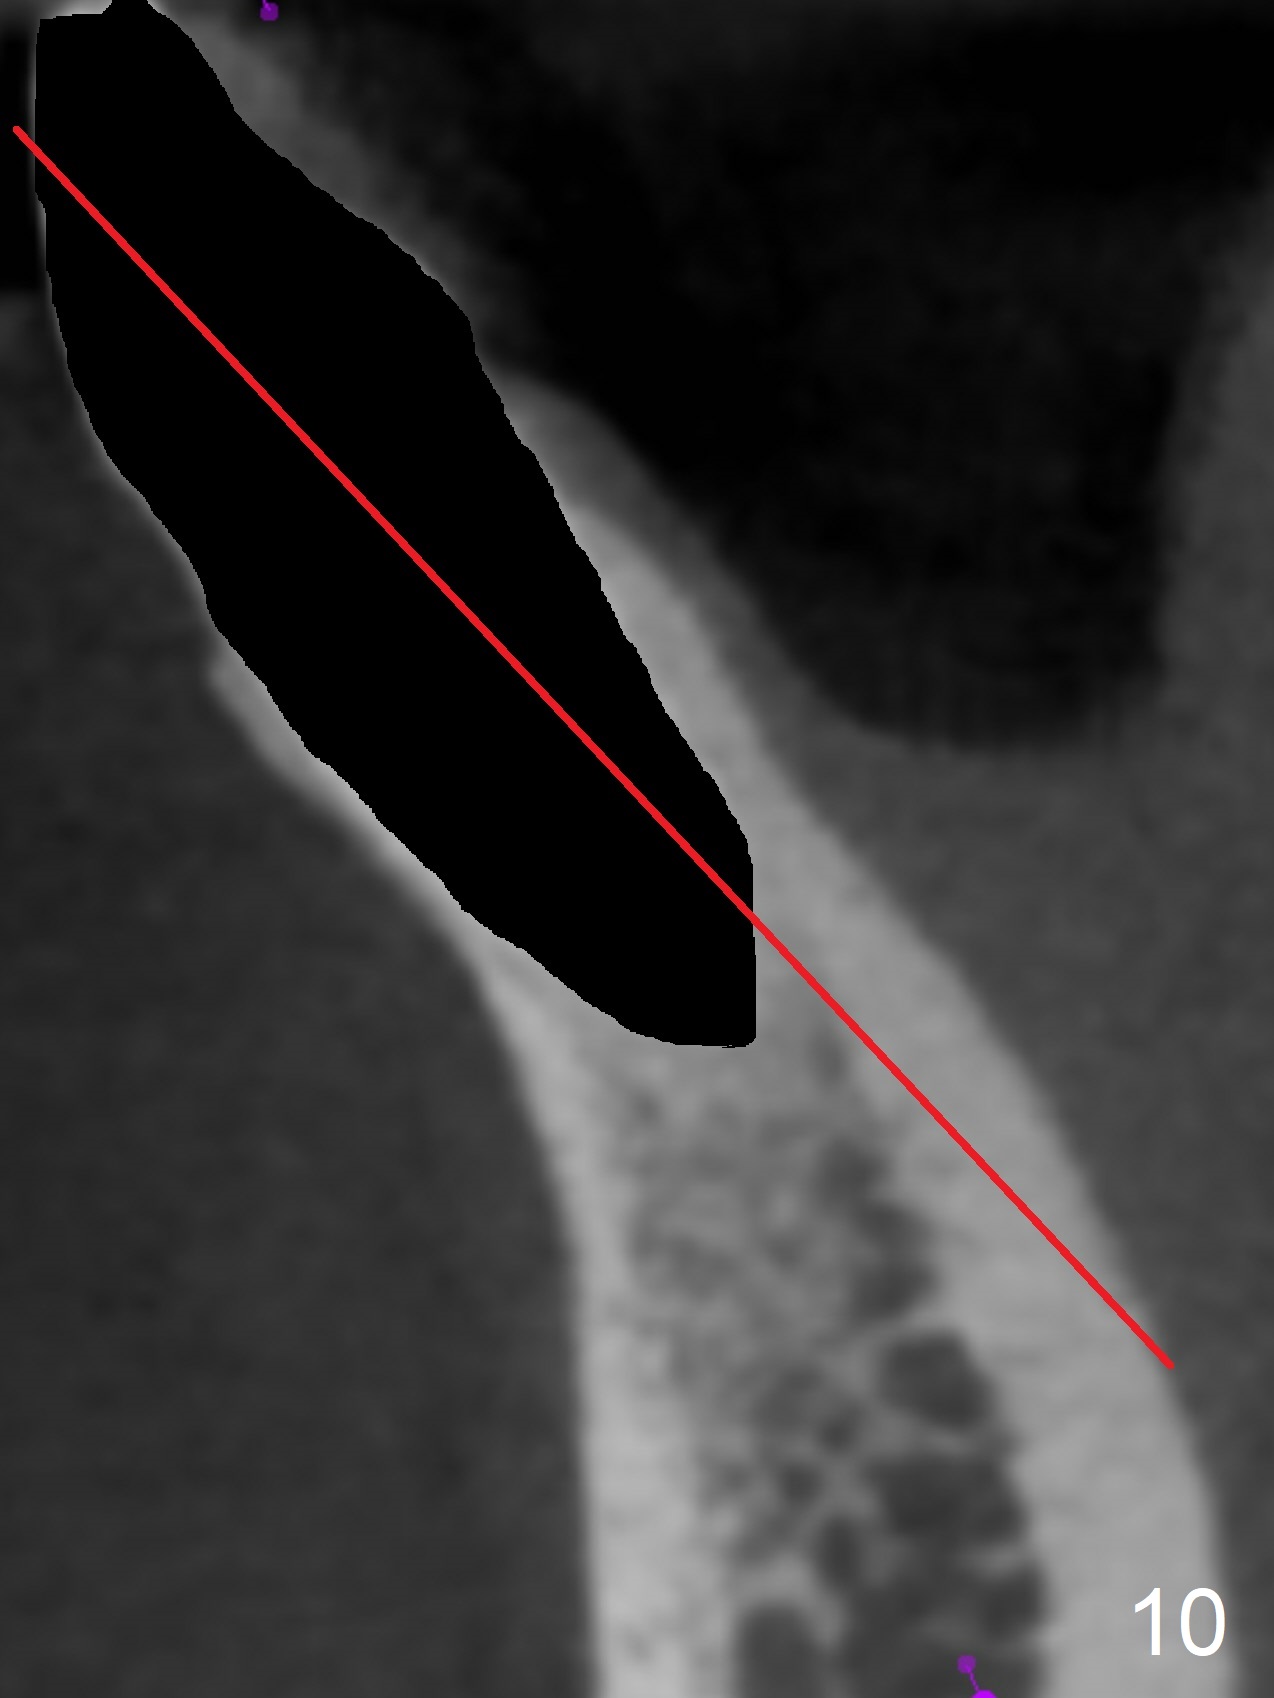

In fact the apex of the lateral incisor is also in the center of the alveolus (Fig.9 *). Osteotomy established in the lingual slope for a long distance (Fig.10,11) will perforate the lingual plate. The correct method of osteotomy is to set up in the middle of the socket and along the long axis of the alveolus with 2 fingers holding the alveolus (Fig.12 (2 circles)). The problem for this case is to use the lower RPD as a guide. With the RPD in place, the tactile sensation is lost.

After change in abutment at #27 and abutment height adjustment at #26 and 27 (Fig.13), splinted provisional is fabricated with clearance from the RPD (Fig.14) and seal of the sockets (Fig.15). Acute submandibular and submental cellulitis develops with sublingual purulent discharge 1 month 10 days postop (Fig.16). CT confirms lingual plate perforation at both sites (Fig.17,18; red line: original socket). With block anesthesia, removal of these implants causes mild discomfort. With Hydrogen Peroxide and normal saline copious irrigation, pain reduces when anesthesia subsides. Bone graft will be placed at the sites approximately in 2 weeks. In fact the infection is not controlled until 2 weeks later (Fig.19). The clasp has to be covered with acrylic for comfort (Fig.20). The previous implant sites heal 1.5 months post implant removal (Fig.22).